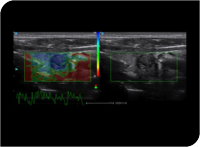

- Category: Color Doppler

Elastography: Elastography is adopted to visualise the stiffness of tissues in real time by delivering an external compression on the tissues. Stiffness of the tissues can be clearly identified by colour codes.